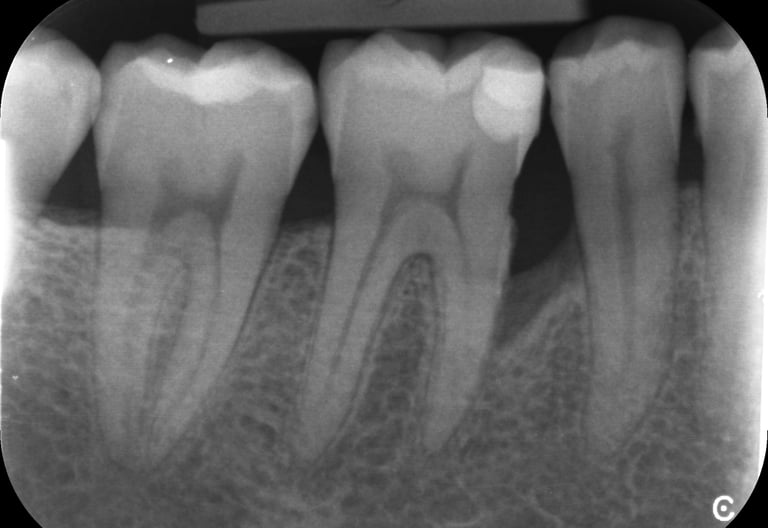

Grâce aux vignettes cliniques, vous découvrirez des situations et radiographies concrètes, vous permettant d’appliquer directement ces recommandations dans votre pratique quotidienne.